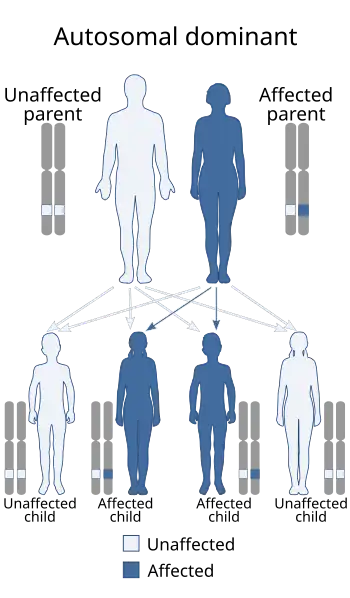

| Ischiopatellar dysplasia is inherited in an autosomal dominant manner[2] | |

Ischiopatellar dysplasia (Small patella syndrome[1])is a rare autosomal dominant[3] disorder characterized by a hypoplasia of the patellae as well as other bone anomalies, especially concerning the pelvis and feet.[4]

Ischiopatellar dysplasia is often considered a familial condition.[20][21][22][23] Ischiopatellar dysplasia has been identified on region 5.6 cM on chromosome 17q22. Mutations in the TBX4 (T-box protein 4) gene have been found to cause ischiopatellar dysplasia due to the essential role TBX4 plays in lower limb development since TBX4 is a transcription factor.[24]

Ischiopatellar dysplasia is sometimes referred to as Scott-Taor syndrome after the researchers who first described ischiopatellar dysplasia as they recognized it in a family as an autosomal dominant disorder in 1979.[28] This finding was important as they were the first to note that it was a benign disorder that is separate from the more severe nail-patella syndrome.[29] Other common names for ischiopatellar syndrome are small patella syndrome (SPS), since the patellae are often small or absent in patients who have this syndrome, and coxo-podo-patellaire syndrome.[30][31][32]